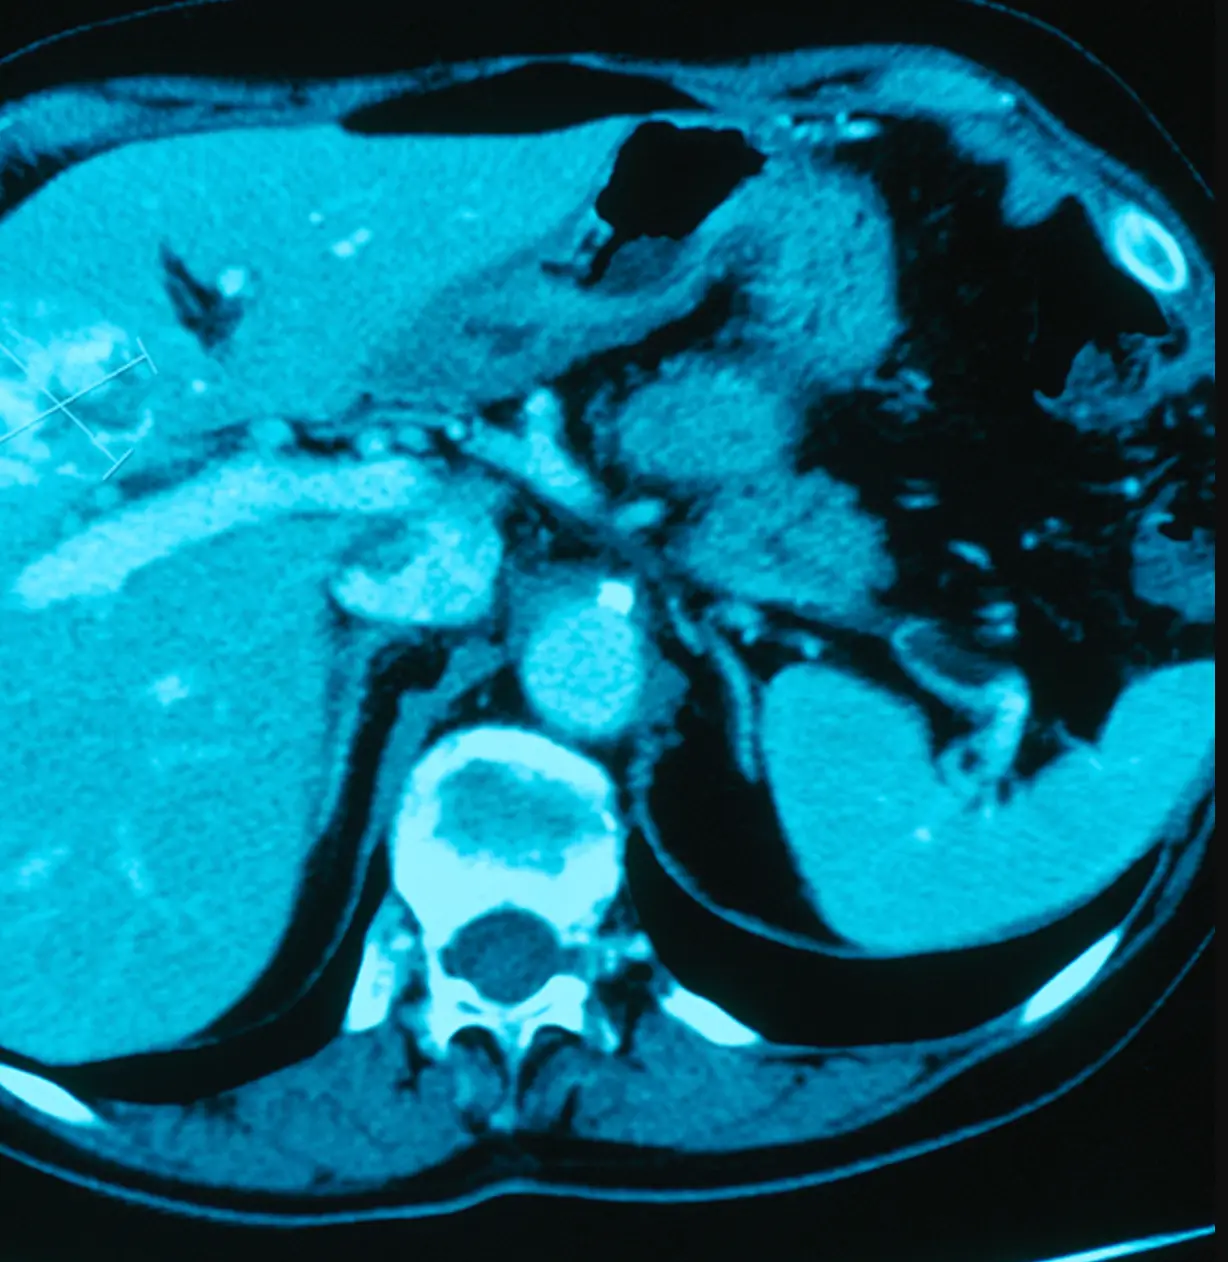

The parasites are native to fresh water fish in the Mekong region, leaving Isaan to have the highest reported instance of cholangiocarcinoma, or bile duct cancer, in the world due to the heavy consumption of the raw fish meal.

The 'silent killer' disease has one of the lowest survival rates of all cancers if left untreated by surgery.